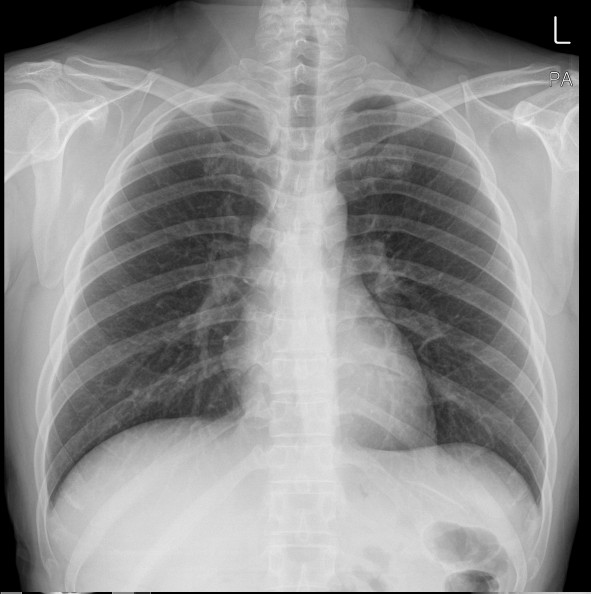

왼쪽 갈비뼈 아래 통증 지금부터 왼쪽 갈비뼈 아래 통증의 주요 원인 10가지,

하나씩 아주 자세히 설명드릴게요.왼쪽 갈비뼈 아래 통증